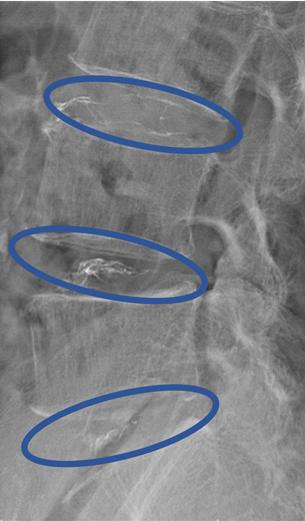

DiscoGelを入れた後の画像になります。

治療は 40分程度で終了

回復室で休憩後、歩いて帰院されました。